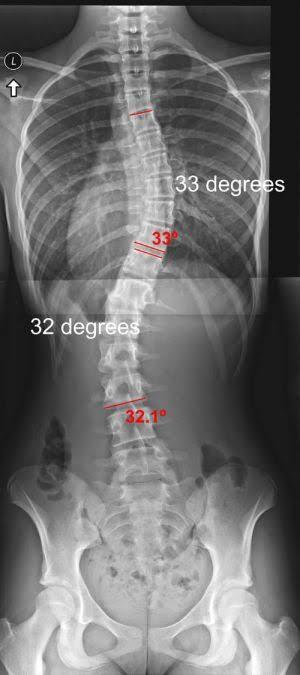

pic x-ray